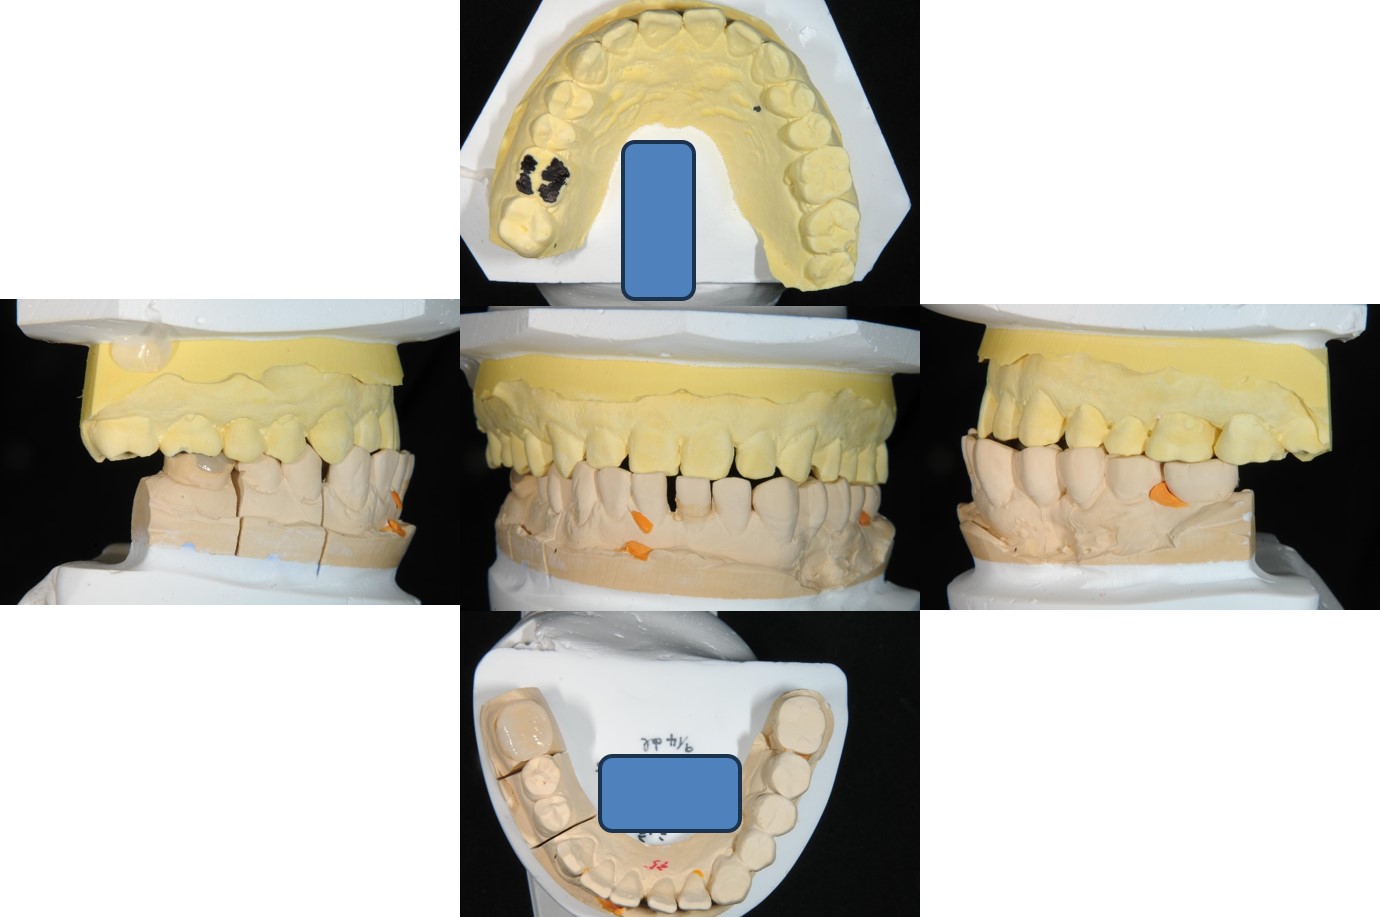

上面弓、上咬合器